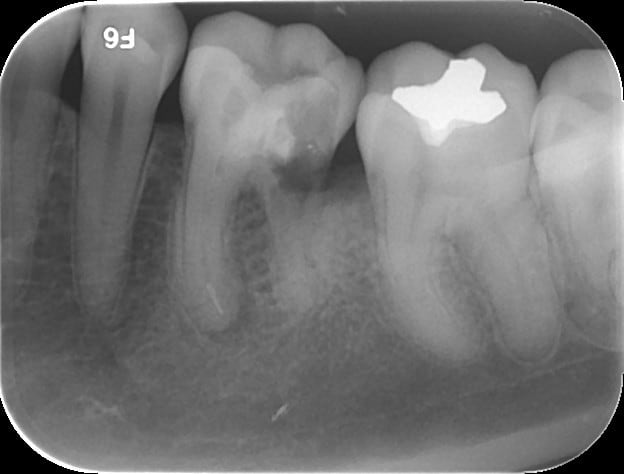

Parfois, les soins conservateurs aboutissent plus rapidement à des lésions apicales... 36 et 46 même patient, même résultat! Arrivé en urgence avec une cellulite très importante côté de gauche...

N crose pulpaire 46   01122014 vjykji - Eugenol

N crose pulpaire   11122014 m74z40 - Eugenol

N crose pulpaire   01122014 acyqev - Eugenol